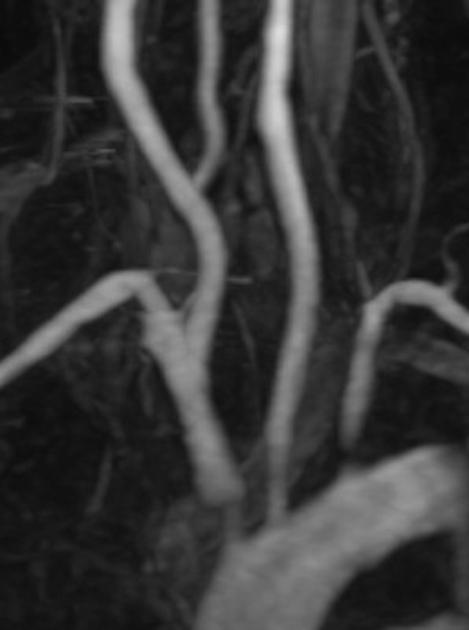

Radiographic features

CT/MRI

Findings include 2:

wall thickening: active acute phase

wall enhancement: active acute phase

aortic valve disease: stenosis, regurgitation

occlusion of major aortic branches

aneurysmal dilatation of the aorta or its branches

pseudoaneurysm formation

diffuse narrowing distally (i.e. descending and abdominal aorta): in the late phase

The pulmonary arteries are also commonly involved, with the most common appearance being peripheral pruning.